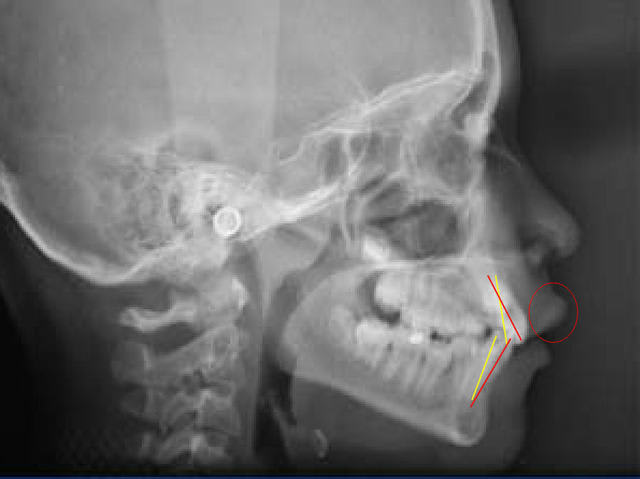

Voici une analyse très succinte, mais parlante, du cas que tu caractérises comme "birétro".

En rouge, position actuelle des axes des incisives.

Regardez aussi la projection déjà presque excessive de la lèvre supérieure par rapport au nez.

La position à donner aux incisives peut aller du jaune au rouge. En arrière du jaune : trop en arrière, en avant du rouge : trop en avant.